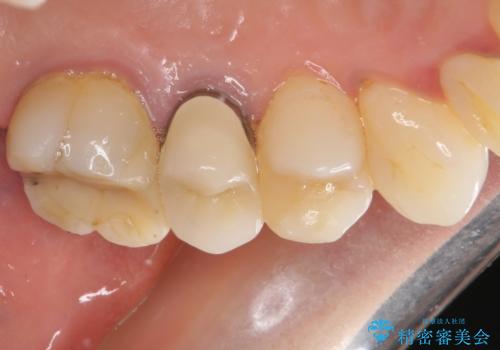

仮歯に変えた後にオールセラミッククラウンにて補綴することとしました。

治療前と比べてとても自然な前歯となり、患者様には大変満足していただきました。